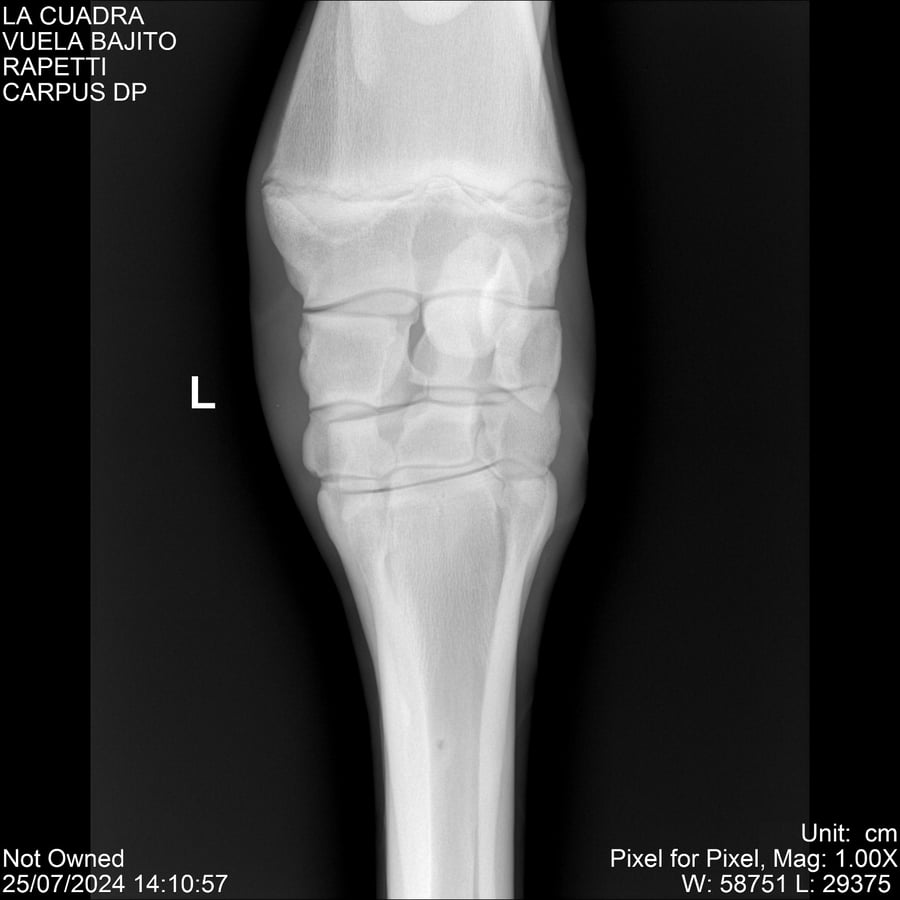

LOTE 16, VUELA BAJITO Lote Anterior Volver al remate Lote Siguiente Ficha Contacto Montevideo - Ficha del Lote Identificador: #284451 Categoría: Yeguarizos Montevideo - 77 Visualizaciones ClicData Contacto Empresa: Abelenda N. R., Walter Hugo Nombre*: Teléfono* : E-mail* : Mensaje Enviar Registrese gratis Este contenido Exclusivo está disponible sólo para usuarios registrados Ingresar